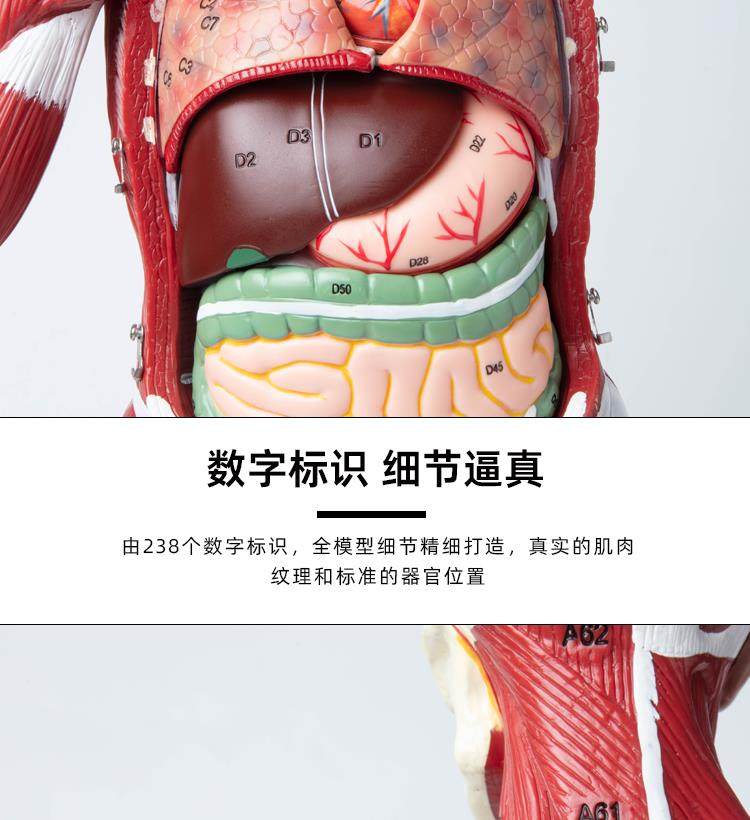

Human Body Muscle Internal Organ Disassembly Anatomy Structure Model Tissue Exercise Artificial Medical Teaching Aids

| Color Classification | 85 Human Muscle Internal Organs Removable Organ,50cm Muscle Model |